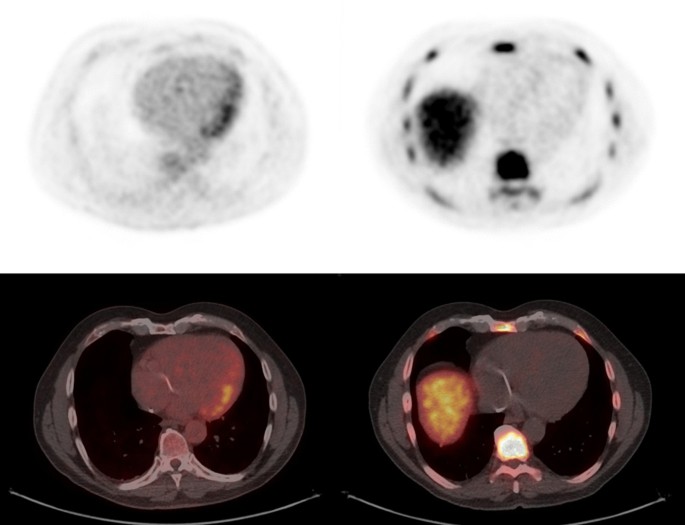

Figure 1 shows an example of whole-body FLT and FDG studies in the same subject with sarcoidosis and evidence of active CS and NS. Agreement between FLT- and FDG-PET for the assessment of individual sites varied but was highest for cardiac [κ = 0.86 (95% CI 0.59–1.0)] and CNS (spinal/paraspinal) [κ = 1.0 (95% CI 1.0–1.0)] involvement (Table 2). Agreement for the involvement of lung parenchyma was good [κ = 0.69 (95% CI 0.29–1.0)] while the agreement for the total number of affected sites was excellent [ICC = 0.78 (95% 0.45–0.93)]. Overall, agreement between FLT- and FDG-PET for the diagnosis of active sarcoidosis was excellent (κ = 0.76 (95% CI 0.32–1.0), Table 3). Inter-observer agreement for active sarcoidosis was excellent for both FLT and FDG (κ = 0.81 (95% CI 0.46–1.0) vs κ = 1.0 (95% CI 1.0–1.0, respectively), Additional file 1: Table S1).

A single case of NS was positive on both FLT and FDG (subject #4); however, FLT-PET was able to identify two paraspinal (Fig. 7) and one intracalvarial lesions (Fig. 1), while FDG-PET only detected the paraspinal lesions. The agreement between FLT-PET and FDG-PET for the diagnosis of active NS was excellent [κ = 1.0 (95% CI 1.0–1.0)] (Additional file 3: Table S3).